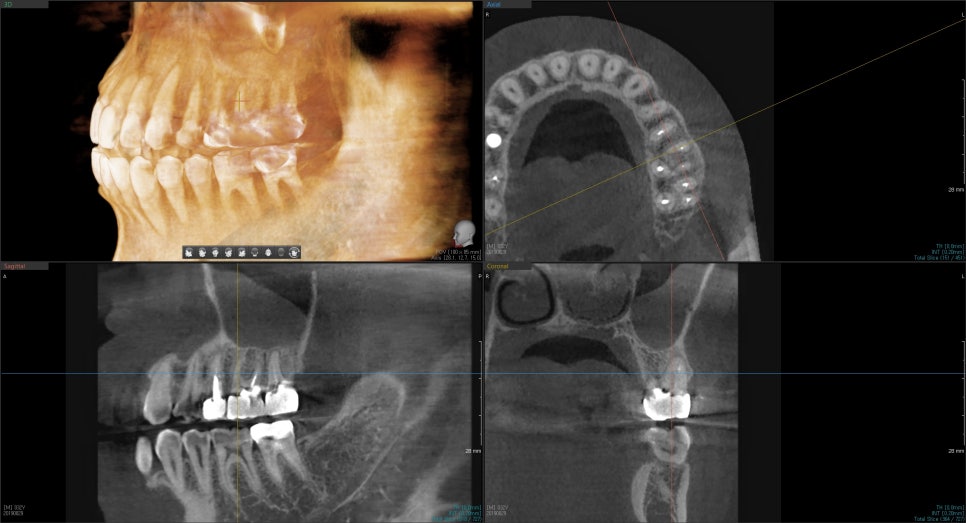

청소가 깔끔하게 되었는지

CT 촬영을 통하여 좀 더 정확히 살펴봅니다.

송파 치과 에서 꼼꼼히 제거해드리며,

텅 빈 공간을 여러번 소독 후,

충전재료로 다시 채워드리기로 했습니다.

이때, 다행스러웠던 것은

포스트라는 것을 하지 않아도 되었다는 것이죠.

그정도로 심하게 약해진 이는 아녀서